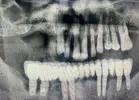

Implant treatment

Periimplantitis

Peri-Implant Mucositis